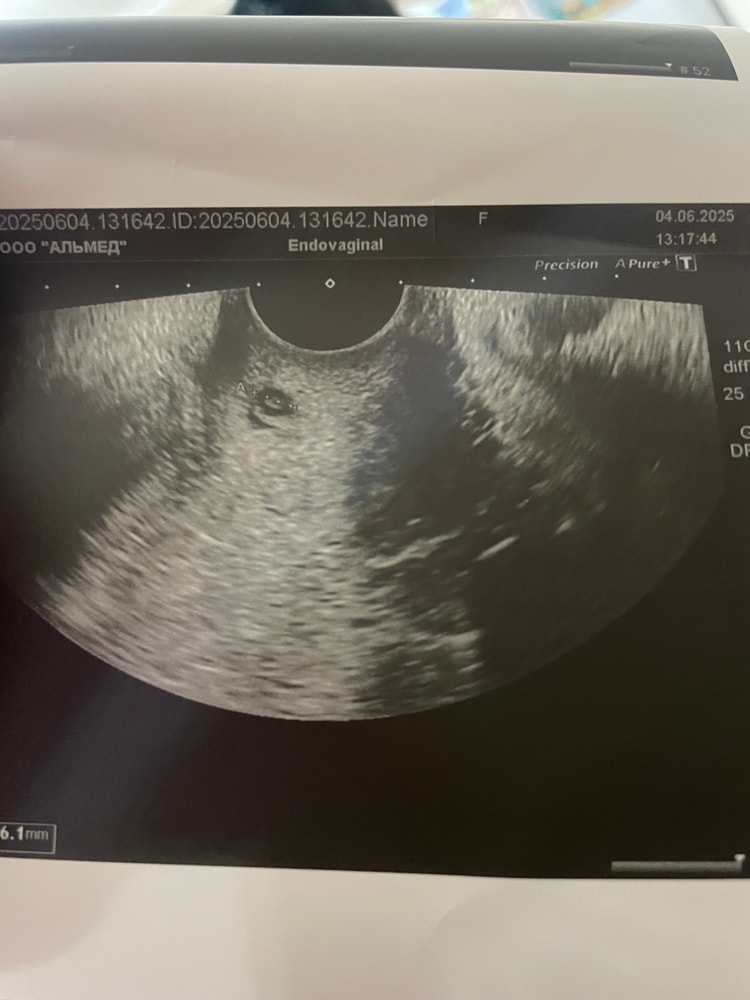

Честно говоря, очень мало похоже на Б (по крайней мере на фото из моего УЗИ так Б не выглядела).

Это УЗИ на 12 день задержки

Сложно сказать по фото . Вроде и похоже , а вроде и место какое то в матке странное ) но я кисты не видела , как выглядят ) на плодное яйцо похоже , но обычно его описывают на узи , если узист видит , НО там видите внутри темное , если бы это было плодное яйцо это был бы эмбрион и у него было сердцебиение, которое невозможно пропустить . Сделайте новый тест )

Но похоже на плодное яйцо очень 😅но опять непонятно чего это снимок ) матки или нет

Череппааашка по имени Натааашка , при низком ХГЧ ничего там не видно кроме плодного яйца, но оно наоборот должно быть темное, а там что-то внутри🤔 и да, матка ли это на кадре 🤷🏼♀️

Татьяна, задержка больше недели . Крайние были 25 апреля , тест за день до задержки был с Легкой тенью , больше не делала , дабы не расстраивать себя . Решила ждать до недельной задержки . По узи сказала что есть несколько маленьких кист , на них тоже есть отдельные снимки узи

А вот про этот ни слова

Хгч в понедельник то сдам , но в интернете по фото выдает только плодное яйцо

Зарина , при таком низком хгч (а он низкий судя по тесту), плодноно яйца быть не должно. Скорее это киста на фото